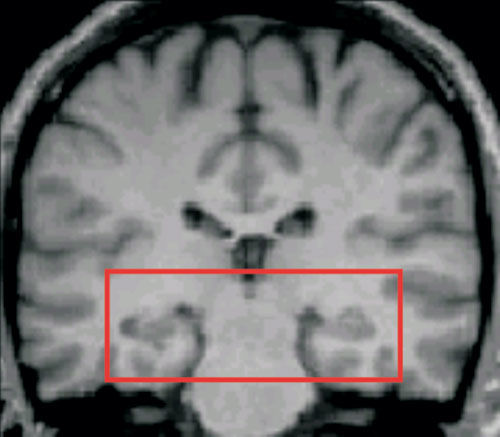

1. A study conducted by Maguire et al. in the year 2000 utilizes MRI scans to investigate the relationships between biological factors and behaviour

1. The aim was to investigate whether or not the hippocampus plays a role in human spatial memory

1. The target population were London taxi drivers with a two-year training course and healthy males who did not drive taxis.

1. The procedure was to scan the structure of their hippocampi of both the taxi drivers and the healthy men.

1. As a result taxi drivers left and right hippocampi had a larger volume compared to the non-taxi drivers. Some parts of the hippocampi were smaller in the taxi drivers.

1. Maguire concluded that there was probably a redistribution of grey matter in the hippocampi of taxi drivers due to the regular use of the spatial memory skills required to remember roads; the neurons are stronger in areas of the brain which are used most.

1. Biological Factor linked back to brain areas, such as hippocampi. Behavior linked back to memory.